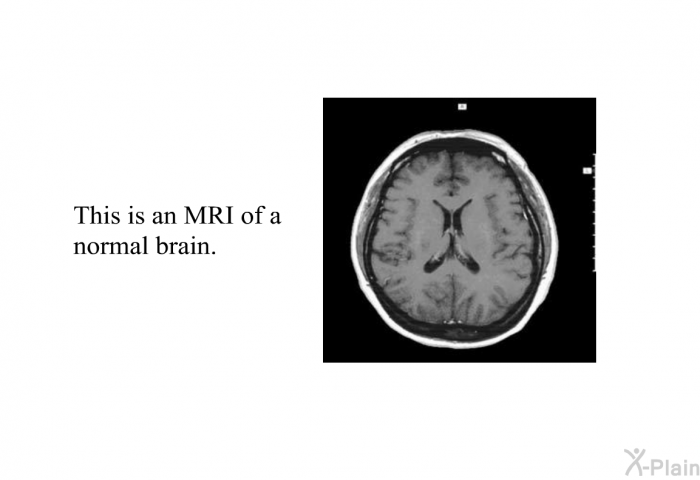

This is an MRI of a normal brain.